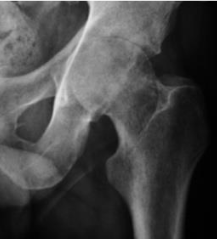

2-year-old child, presented with acute hip pain and tenderness for 2 days, +ve Hx of low-grade fever.

Affected his gait, No hx of recent trauma or injury, no hx of skin rash or UTI

labs show (normal WBC, ↑ ESR)

On examination: A hip is Flexed, ABducted, and Externally Rotated.

(X-ray attached)

A

Transient synovitis